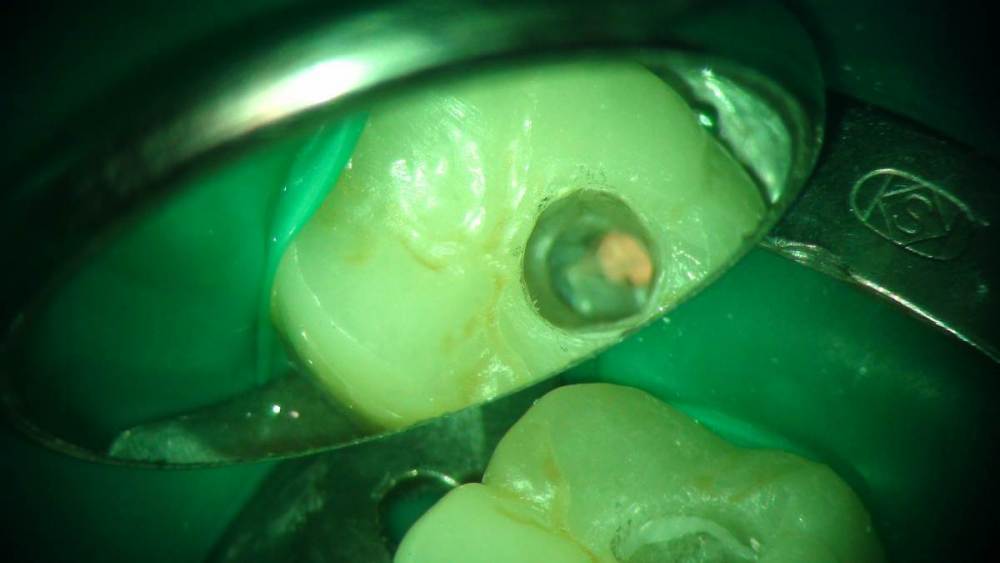

Ico Опубликовано 19 марта, 2022 Автор Поделиться Опубликовано 19 марта, 2022 Микродоступ того не стоит,есть адекватный доступ для адекватного и без рисков эндо.В данном случае мартенситных еще тогда не было,столкнулся с проблемами в виде ступеней,паковкой,потратил больше времени чем хотел,2 визита по 2 часа.Диагноз - хронический пульпит в обострении.Материалы - пре реисы и патфаилы,ковер до 15к,упор на 25к.Паковка волна. 3 1 Ссылка на комментарий

Ico Опубликовано 5 апреля, 2022 Автор Поделиться Опубликовано 5 апреля, 2022 Обострение хронического периодонтита зуб 36. После первичного эндо пропущен ДБ канал,зуб был восстановлен циркониевой вкв + циркон коронка.На пропИл до устья ушло 5 боров.Мед мех стандартный 40к+F1,паковка гибрид с Эйчем.2 визита по 2 и 1.5 часа. 3 1 Ссылка на комментарий